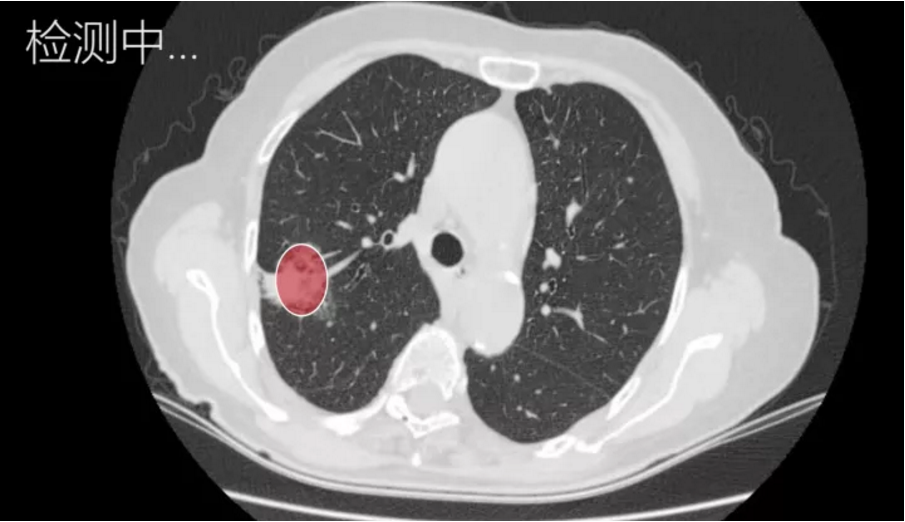

2. 肺癌智能诊断产品

我们的团队基于大数据、深度学习技术以及一流的软硬件平台架构设计,深度结合各医院原有影像系统,开发出一套智能诊断产品,对肺部高分辨率电子计算机断层扫描(HRCT)的结果进行实时自动分析。分析结果自动附加于医生诊断界面,让医生快速定位疑似病灶所在区域,并给出人工智能判断的肿瘤恶性概率。

此外,产品可自动生成影像学报告,描述病灶大小,形态,位置等特征。医生可于此基础上稍作修改,节省医生大量时间的基础上可降低漏诊率,减少报告时间,让患病病人更早的接受下一流程的诊断与治疗。整个一套系统包括后端的服务器,数据库,人工智能算法平台,以及前端的可视化界面,云平台。目前无相关上市产品,本产品填补了国内与国际的空白。